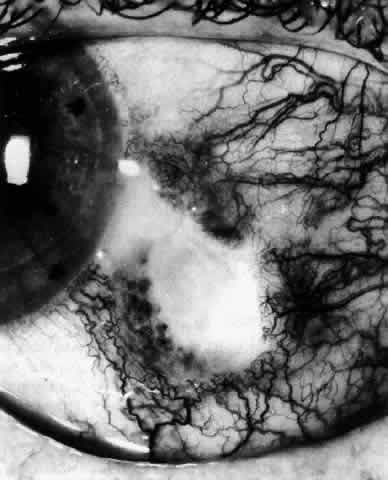

The characteristic features of necrotizing scleritis on fluorescein angiography are hypoperfusion and, eventually, nonperfusion of the vascular networks (Figs. 40 through 43).26 The initial changes are on the venous side of the capillary network; the transit time of the dye increases even if the eye is red and congested. If the disease process persists or has been present for a long time, thrombosis and permanent vaso-occlusive changes occur. These vessels (or the occluded capillary network) are bypassed by the opening of anastomotic channels. New vessels in a granuloma give rise to deep intrascleral leakage of dye (see Fig. 43). Conjunctival and episcleral involvement by the destructive change is late but is always preceded by vaso-occlusive changes that can sometimes be detected with use of the red-free light on the slit lamp (Figs. 44 and 45).

Fig. 40. Early necrotizing scleritis. There is characteristic yellow discoloration of the sclera underlying the conjunctiva at a point of necrosis. In this instance a small filament of tissue has penetrated the conjunctiva.

Fig. 41. Late stage of fluorescein angiogram adjacent to the site of necrosis in the same patient as in Figure 40. Although the eye is uniformly congested, the area near the necrosis shows vascular shutdown, whereas the rest of the conjunctiva and episclera is normally perfused.

Fig. 42. Late arterial phase of fluorescein angiogram in a patient with necrotizing scleritis. All the vessels except the main trunk and the vessels around the limbal perforating vessels are occluded and remain unperfused throughout the angiogram.